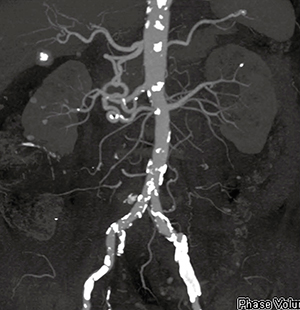

症例2は,79歳,男性,腎盂がん症例である。eGFR が29mL/min/1.73m2と高度に低下しているため,通常は造影CTの適用が困難であるが,手術は腹腔鏡下に行われるため,術前の血管評価がどうしても必要となった。そこで,寝台のスムーズな加減速による連続Spiral Scanによって経時的データを取得し,4D Imagingを行うAdaptive 4D Spiral Plusを用いてわずかな造影剤で造影CT検査を施行した。

撮影は70kVの10フェーズとし,370mgI/mL製剤をテストインジェクションでは3mL,本撮影では20mL使用し,3.9mL/sで注入した。動脈相では末梢動脈まできわめて明瞭に描出されている(図4)。また,連続撮影により静脈相も得られ,動静脈を組み合わせたVR画像も作成可能であった(図5)。

図4 症例2:Adaptive 4D Spiral Plusによる

動脈の描出

図5 症例2:Adaptive 4D Spiral Plusによる動静脈VR画像